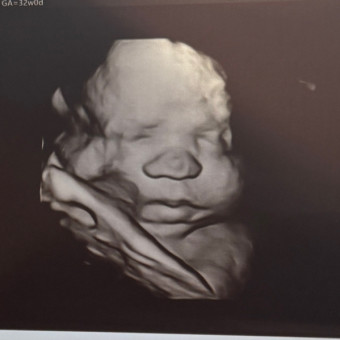

Owen

Megan Hillman

Lackawanna, NY

October 31, 2025